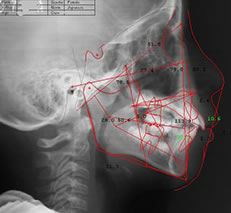

セファロとは首から上の骨格を調べる矯正治療専門のレントゲンです。頭の正面と側面を撮影して歯を支えている顎の骨の大きさや位置、歯の角度や口元と顔とのバランスなどを分析します。

この撮影により、矯正治療で歯をどれくらい移動させるのかを数値的に判断することができ、矯正治療の難易度の把握や治療の精度を高めるのにも役立ちます。